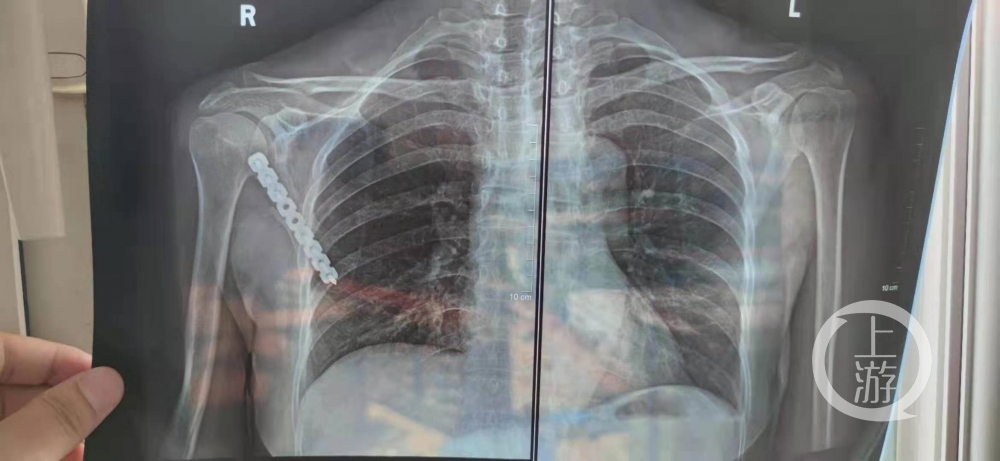

上游新闻记者注意到,舒女士左肩胛骨处被缝了13针,CT片显示,其右肩胛骨处安装了固定器械。

▲CT显示,舒女士右肩胛骨安装了固定器械,左边没安装。图片来源/受访者供图